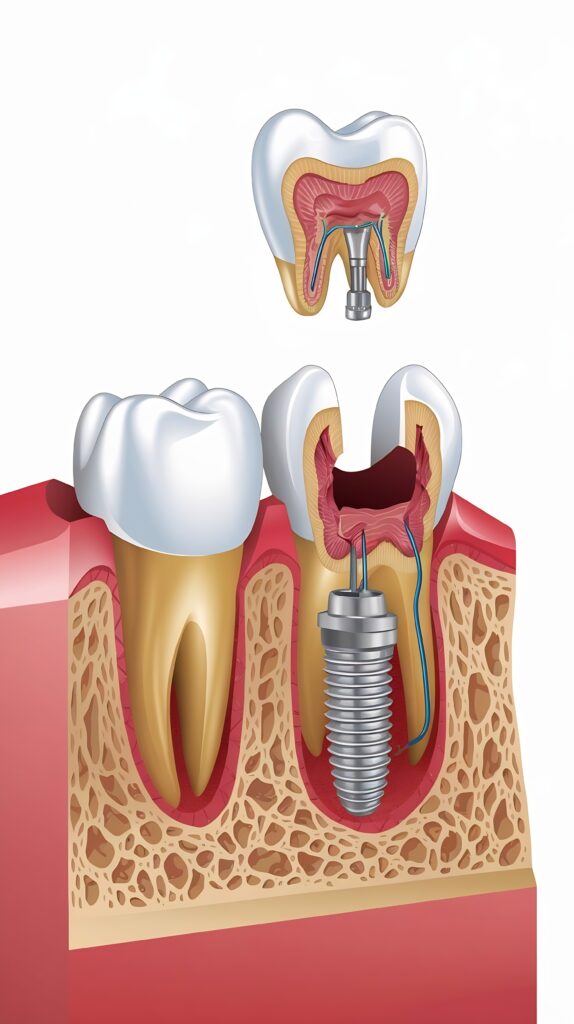

Dental implants are titanium posts that act as artificial tooth roots. They are placed securely into the jawbone to support a crown, bridge, or denture. Because they integrate with the bone, implants provide unmatched stability, durability, and comfort. Whether you’re missing one tooth or several, implants offer a long-lasting and highly aesthetic solution.

At Ivory Dental, The dental implant process is simple, precise, and designed for your comfort. It begins with a thorough consultation and digital planning to assess your needs. The implant is then gently placed into the jawbone, where it naturally bonds over a short healing period. Once healed, a custom-made crown or restoration is attached, completing your new, strong, and natural-looking smile.

Implant Placement

The implant is placed into the jawbone using precise, minimally invasive techniques.

Healing & Integration

Over a few months, the implant fuses with the bone for strong, stable support.